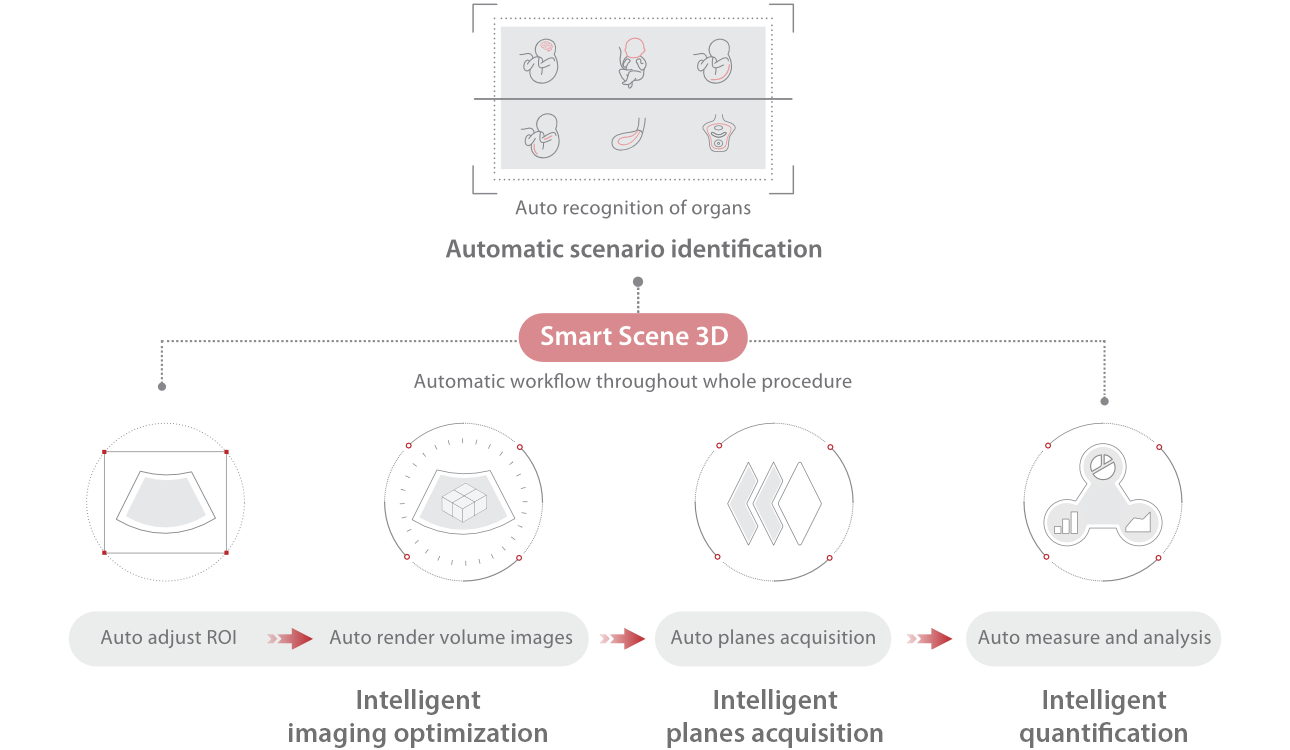

The Nuewa I9 Elite Edition, dedicatedly designed for women and neonatal healthcare, providing an innovative experience from inside out. These innovations are developed based on in-depth insights into complex clinical scenarios, providing accurate and timely answers as well as outstanding efficiency and remarkable user experience